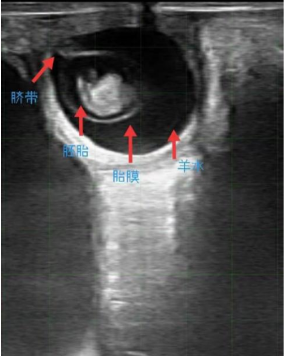

通过B超设备我们可以清晰地看到32天左右的牛胎儿的脐带、胚胎、胎膜和羊水,还可以结合设备影像学对卵巢进行检查,避免手工检查对卵巢的破坏,针对卵巢疾病可以有针对性的采取治疗方案,降低繁殖疾病发生,提高母牛繁殖效率,增加牧场收益。现在市面上B超设备可以用IPAD作为成像现实终端设备,清晰度非常高;机身小巧,对于繁殖人员来说不会因为设备重量而影响工作效率;且可以彩色标记动脉和静脉,还可以在牧场内部开展部分教学演示。